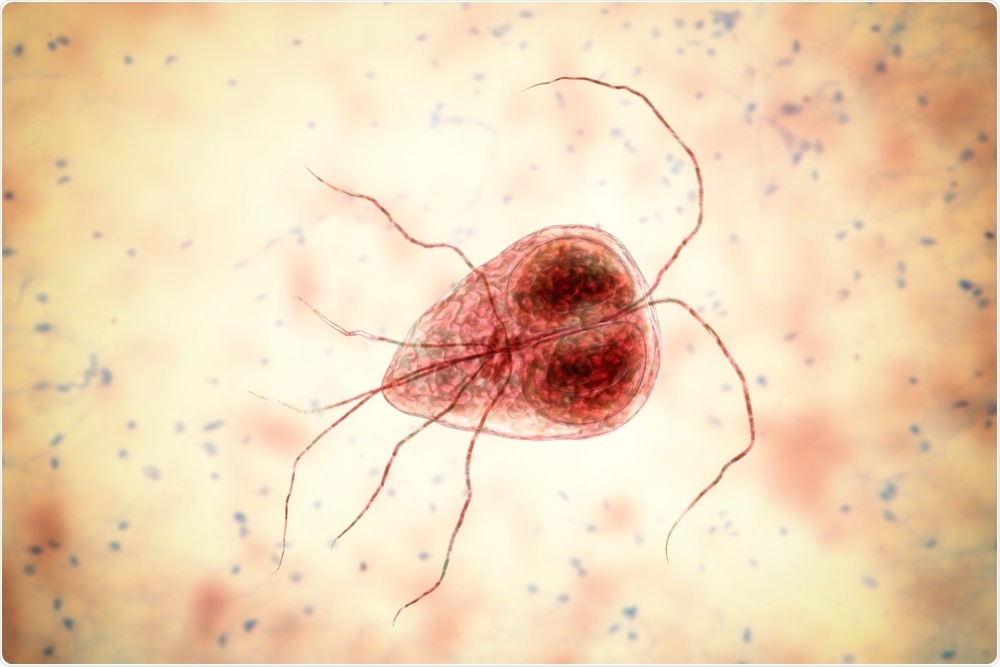

Using NMR to assess anti-malarial efficacy

Malaria is a ruinous infectious disease, causing nearly 500,000 deaths annually. The parasite resulting in more than half of all cases of malaria in humans is the unicellular protozoan Plasmodium falciparum.

As soon as it invades a red blood cell (RBC), it experiences a developmental cycle, the entirety of which is done in 48 hours. This leads to the breakdown of the RBC to discharge new parasites. The protozoa offspring are called merozoites and have the ability to invade a new RBC immediately.

Image Credit: Bruker BioSpin Group